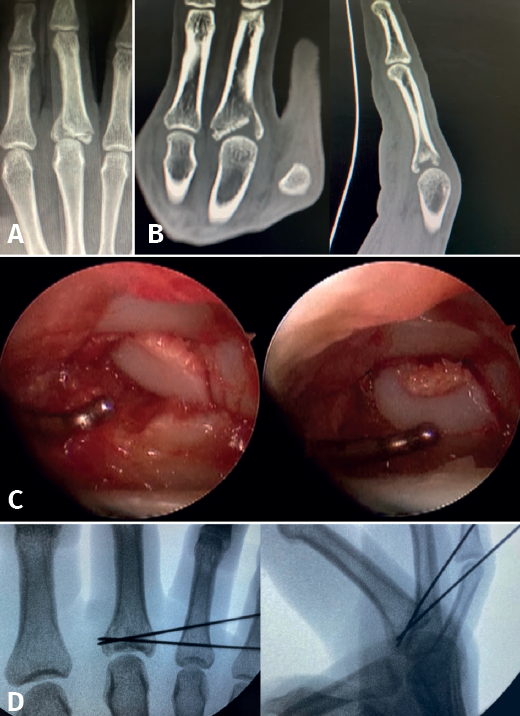

- Fractures with avulsion of the insertion of the collateral ligament (Figures 2 and 3).

- Intra-articular fractures proper, caused by compression or shear mechanisms.

The free osteochondral fragments can be removed with grasping or mosquito forceps.

The main fragments are reduced with the aid of a palpator or a small blunt dissector. External reduction of the fragments may be necessary, especially when they are impacted in the centre of the articular surface. This is especially common at the base of the proximal phalanx. To do this, we introduce a 1.0 Kirschner wire through the fracture site, through an extra-articular "window", and in "joystick" fashion, we lower the impacted fragment. Sometimes it is advisable to check each of the maneuvers using fluoroscopy, which can be positioned perpendicular to the arm or in the traditional manner, which requires us to release the hand of the patient in order to perform the check.

Once the fragments have been reduced, 0.8 or 1.0 Kirschner wires are used to maintain reduction (Figure 7). Sometimes we can only maintain reduction by applying a stop, to prevent the osteochondral fragment from collapsing. Depending on the fracture pattern and the surgeon's preference, we can use conventional screws, cannulated screws, etc. (Figures 8 and 9).